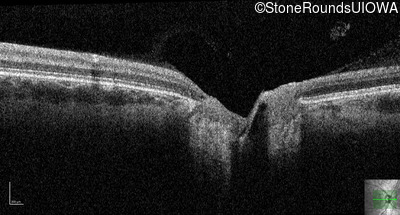

Optical Coherence Tomography - Right - 10/160 +1 sc

Exemplar / OCT Stack

OCT Stack